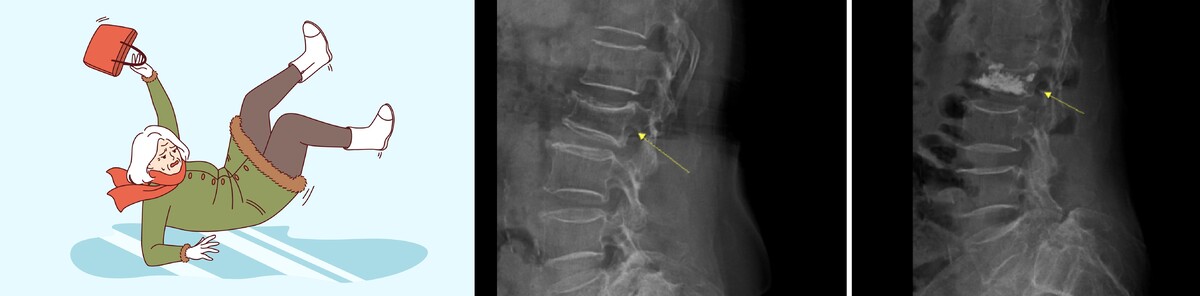

척추 압박골절은 말 그대로 척추뼈가 눌려 주저앉는 형태의 골절을 말한다. 흔히 떠올리는 팔이나 다리 골절처럼 뼈가 두 동강 나는 것이 아니라, 원기둥 모양의 척추체가 납작하게 찌그러지며 통증을 유발한다. 골다공증이 있으면 더욱 쉽게 발생한다.

척추 압박골절의 진단은 기본적으로 X-ray 검사를 통해 척추뼈의 눌림이나 변형 여부를 확인한다. 다만 단순 방사선 검사만으로는 골절의 상태를 정확히 파악하기 어려운 경우가 있어, 통증이 심하거나 신경 손상이 의심되면 CT나 MRI 검사가 필요할 수 있다. 또한 골다공증이 동반된 경우가 많기 때문에 골밀도 검사를 함께 시행해 뼈 상태를 확인하는 것이 치료 방향을 정하는 데 도움이 된다.

반면 통증이 심해 일상적인 보행이 어렵거나 척추체 변형이 진행되는 경우에는 척추체 성형술과 같은 시술적 치료를 고려할 수 있다. 척추체 성형술은 압박골절로 무너진 척추뼈 내부에 특수 바늘을 삽입한 뒤 골시멘트를 주입해 뼈를 단단히 고정하는 원리를 쓴다.

필요에 따라 풍선을 이용해 눌린 척추체의 높이를 일부 복원한 후 시멘트를 주입하기도 한다. 절개 범위가 크지 않고 국소마취로 진행돼 회복이 비교적 빠른 편이며, 고령 환자에게도 적용 가능한 치료법으로 알려져 있다. 다만 모든 압박골절에 동일하게 적용되는 것은 아니며, 골절 형태와 환자의 전신 상태를 종합적으로 고려해 치료 방법을 결정해야 한다.